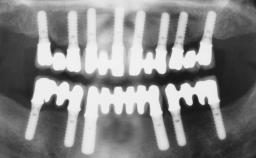

This case features the flapless computer-guided placement of 7 bone-level implants, distributed to provide maximal support for the prosthetic framework. A rigid one-piece metallic framework was utilized as an interim restoration to reduce the risk of fracture associated with this prosthetic design. As part of the clinical examination, the SAC Assessment Tool was used, resulting in a surgical and restorative risk classification as “complex”.